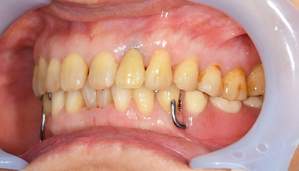

MTM中。頬側には審美面の回復のために仮歯がついています。

歯からはフック、隣り合った歯にはワイヤーが渡してあります。そこにゴムをひっかけて歯を挺出します。